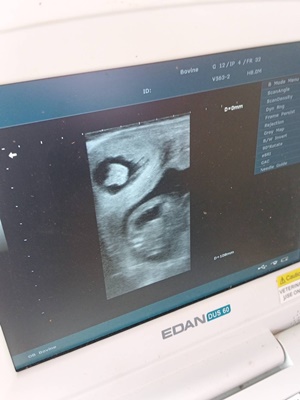

วันที่ 7 ตุลาคม 2568 เวลา 10.00 น. นายพิเชษฐ์ คุณาคำ นายสัตวแพทย์ปฏิบัติการ พร้อมเจ้าหน้าที่สำนักงานปศุสัตว์อำเภอเชียงม่วน จังหวัดพะเยา ให้บริการตรวจท้องด้วยเครื่องอัลตราซาวด์แก่เกษตรกรผู้เลี้ยงกระบือ ในพื้นที่บ้านมาง หมู่ที่ 1 ตำบลบ้านมาง อำเภอเชียงม่วน จังหวัดพะเยา จำนวน 5 ตัว ผลการตรวจพบว่ามีการตั้งท้อง จำนวน 2 ตัว จึงแนะนำการดูแลโคกระบือช่วงระหว่างการตั้งครรภ์ รวมถึงจัดโปรแกรมยาถ่ายพยาธิ ยาบำรุง และแร่ธาตุที่จำเป็นในช่วงท้ายของการตั้งครรภ์ ส่วนกระบือที่ไม่มีการตั้งท้องได้มีการนัดหมายเกษตกรเพื่อแก้ไขปัญหาระบบสืบพันธุ์ต่อไป